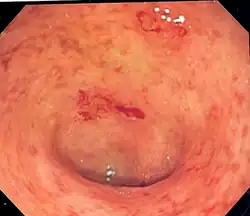

Endoscopic image of a colon affected by ulcerative colitis. The internal surface of the colon is blotchy and broken in places. Mild-moderate disease.

Endoscopic image of ulcerative colitis affecting the left side of the colon. The image shows confluent superficial ulceration and loss of mucosal architecture. Crohn's disease may be similar in appearance, a fact that can make diagnosing UC a challenge.